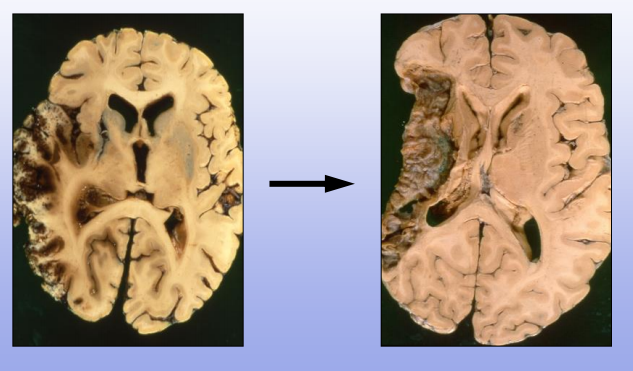

Infarcts evolve over time:

Left: acute MCA infarct, tissue expanded due to edema

Right: months later, infarcted tissue gone, left with cavity